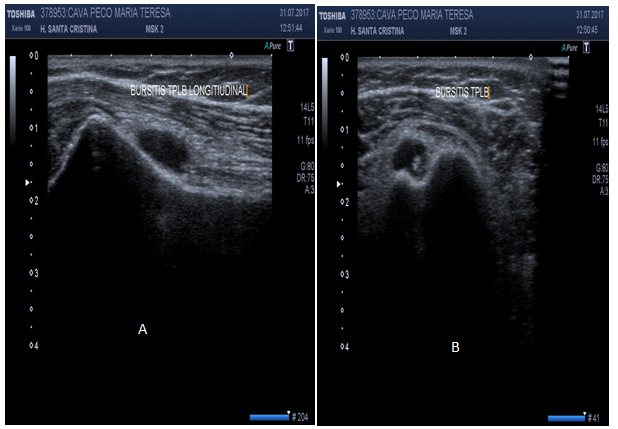

US can ascertain between normal versus diseased bicipital tendon (partial or full tears, tendinosis). Hyperechoic “fluid ring” around tendon may denote tenosynovitis in short axis, whether a “tear sign” may denote tenosynovitis in long axis (Figure 14). US may identify osteophytes in AC joint and joint effusion (“Geyser Sign”) if inflammation subsides (Figure 15). Small calcific areas in the tendon can be observed specially when assessed dynamically (Figure 16). US is highly sensitive to diagnose SASD bursitis, especially if fluid on scan image is greater than 2mm distance (Figure 17). Dynamic evaluation is capable to determine biceps tendon subluxation or luxation and subacromial impingement (Figure 18).

Figure 14 Bursitis of the long head of the biceps in short axis (hyperechoic ring in A) and in long axis (tear sign in B).